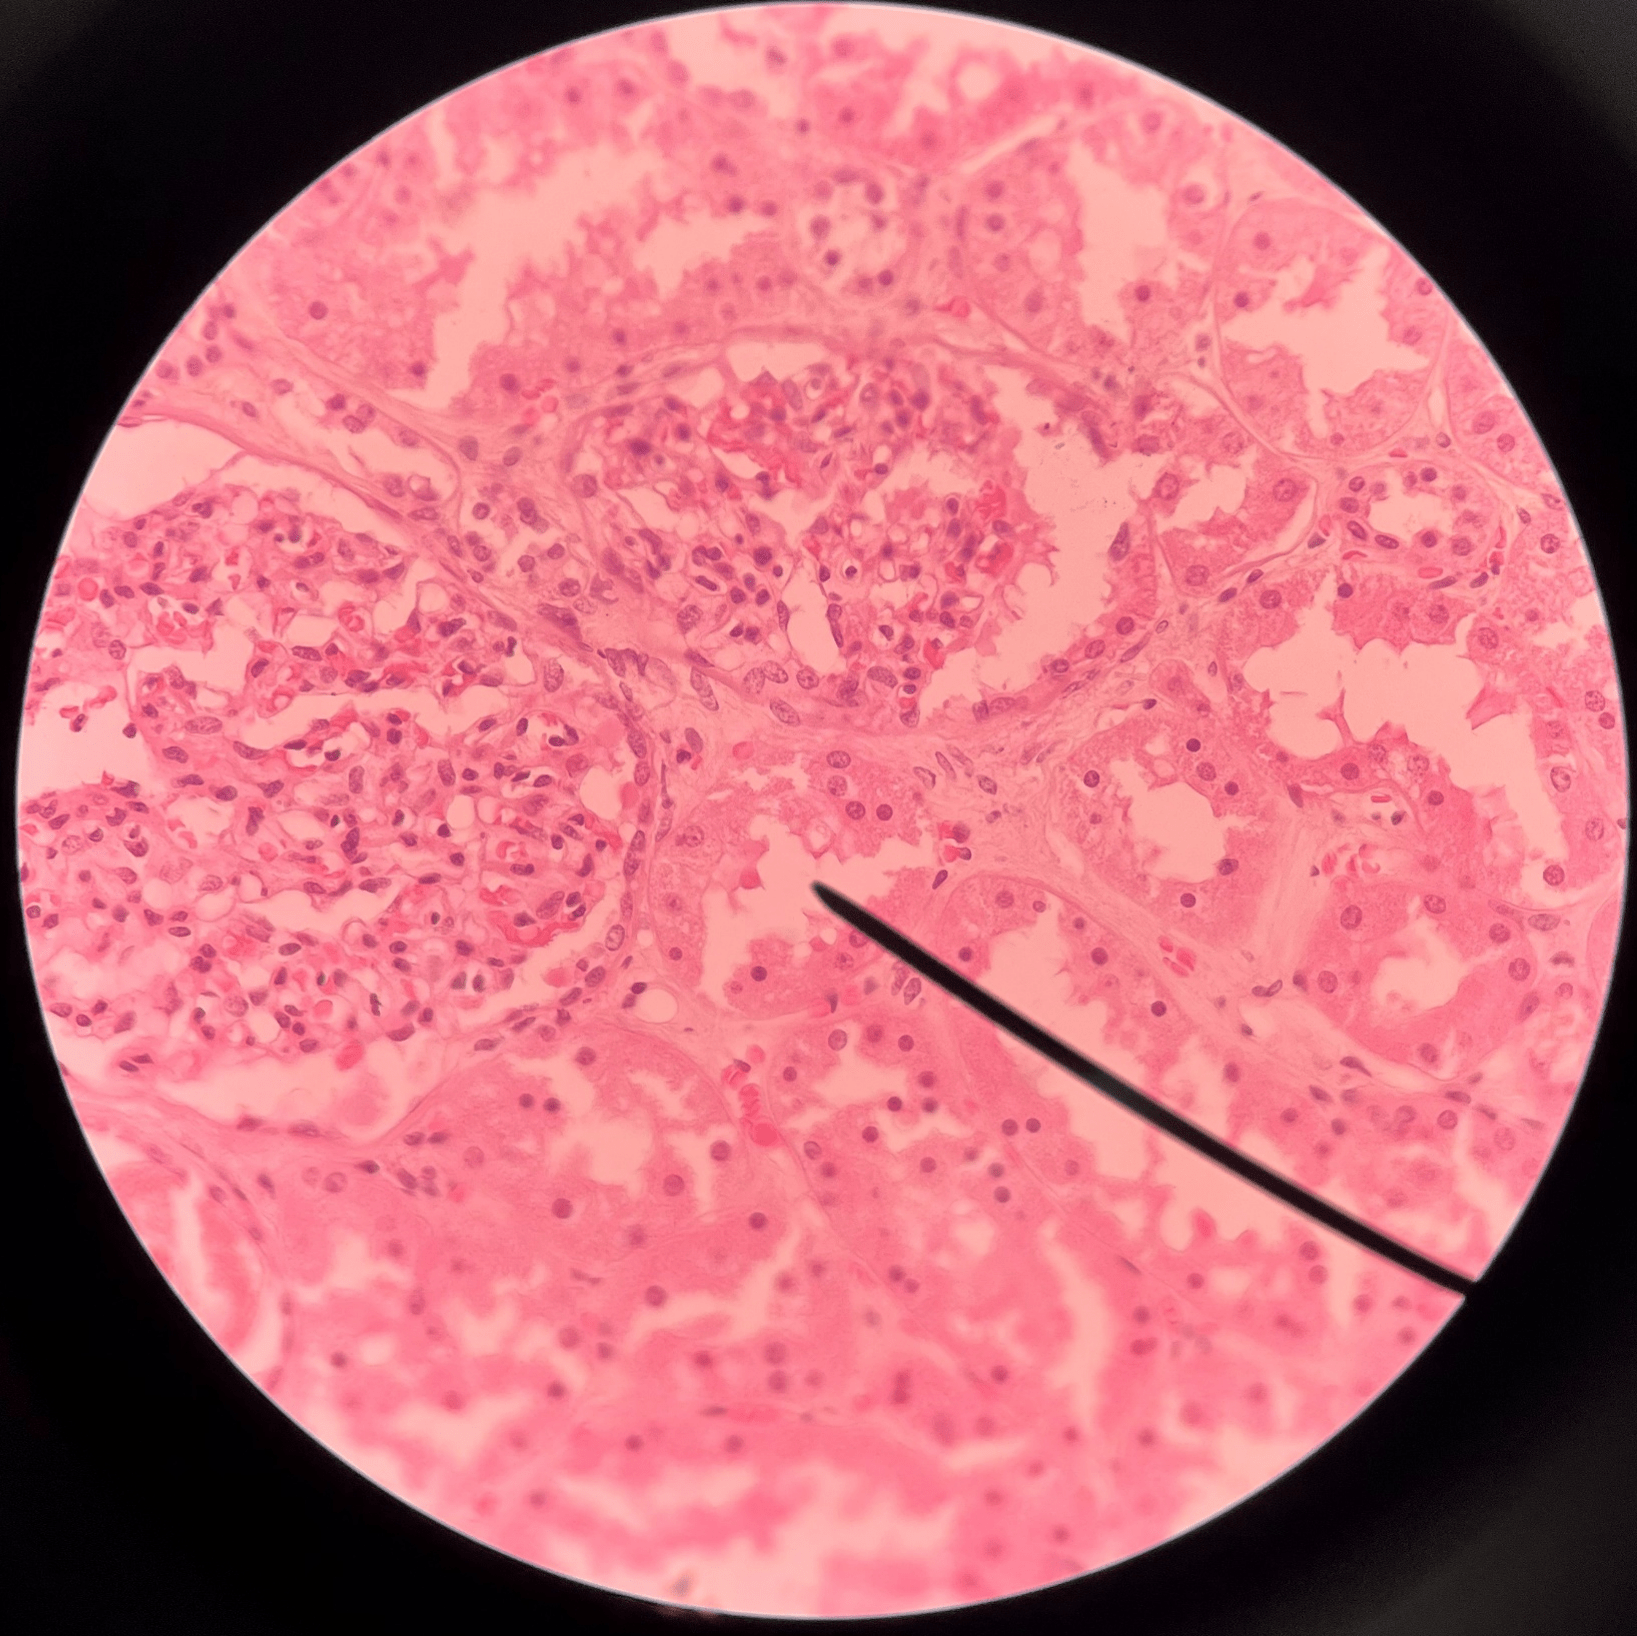

glomerulus

• Slide histology of the nephron.

• Part of a renal corpuscle.

• The capillary network of a renal corpuscle.

• Part of a renal corpuscle.

• The capillary network of a renal corpuscle.

42

New cards

capsular space

• Slide histology of the nephron.

• Part of a renal corpuscle.

• The interior of the glomerular capsule.

• Part of a renal corpuscle.

• The interior of the glomerular capsule.

glomerular capsule

• Slide histology of the nephron.

• Part of a renal corpuscle.

• A wall enclosing the glomerulus.

• Shown in the image is the parietal layer.

• Part of a renal corpuscle.

• A wall enclosing the glomerulus.

• Shown in the image is the parietal layer.

renal tubule

• Slide histology of the nephron.

• Part of a nephron.

• Modifies glomerular filtrate by reabsorption and secretion of water and ions.

• Divided into the proximal convoluted tubule, loop of Henle, and distal convoluted tubule.

• Part of a nephron.

• Modifies glomerular filtrate by reabsorption and secretion of water and ions.

• Divided into the proximal convoluted tubule, loop of Henle, and distal convoluted tubule.